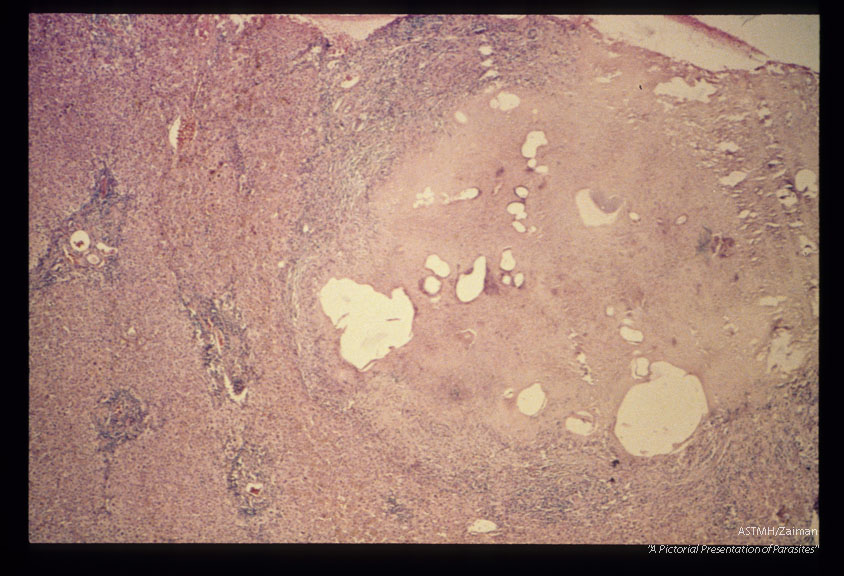

Gross and microscopic photos of human liver from Minnesota where about one half of the red foxes are infected.

Echinococcus multilocularis

Description: Gross and microscopic photos of human liver from Minnesota where about one half of the red foxes are infected.